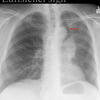

Luftsichel sign

LUL collapse; hyperinflated LLL